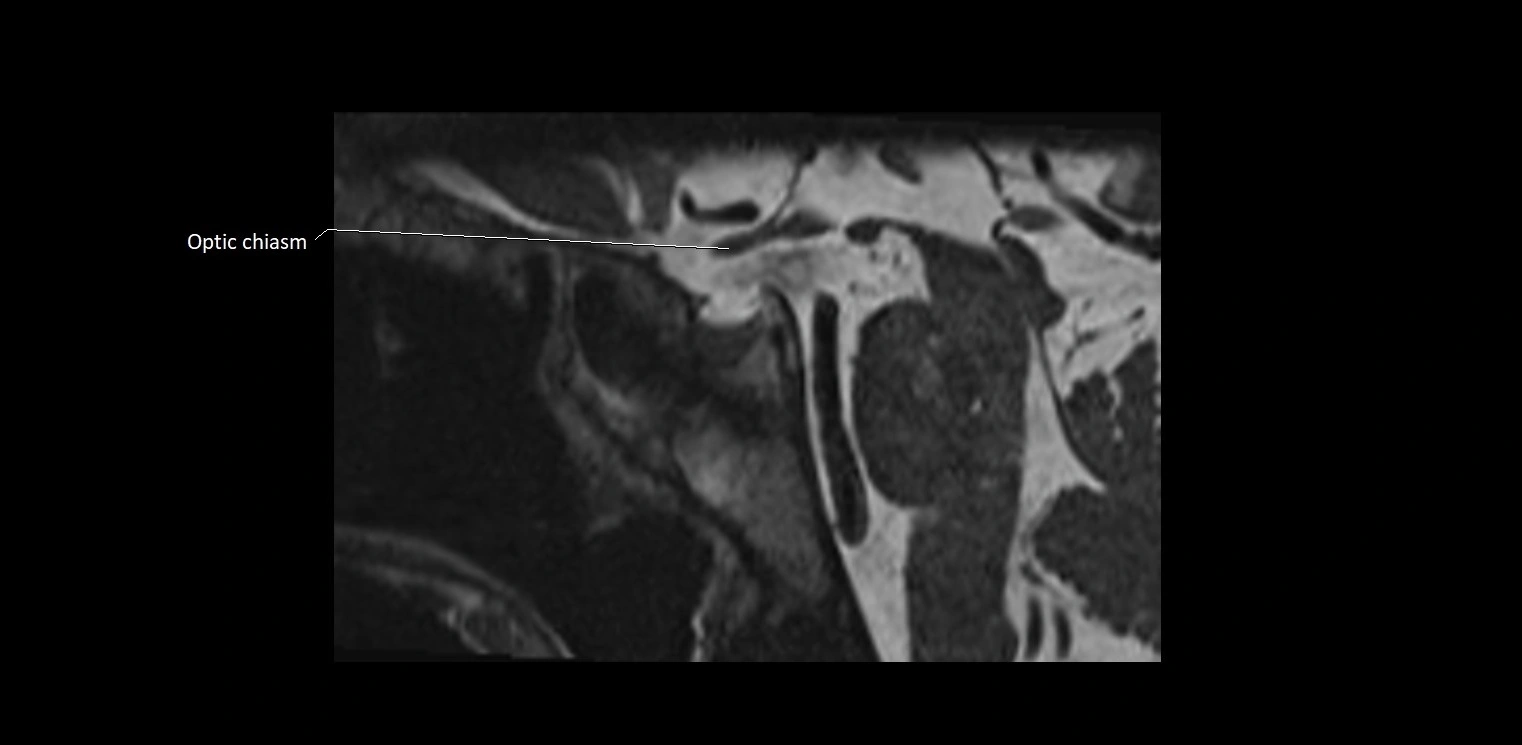

MRI images

image